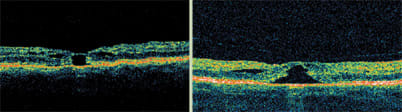

Laser treatment becomes less effective when cysts are present, as in this case of diabetic cystoid macular edema.

Another characteristic that we look for in DME is the presence of cysts. When cysts develop in the macula, laser treatment becomes less effective. Steroids or anti-VEGF agents are usually a better treatment choice. Over time, cysts coalesce and become larger and larger. The larger they become, the less likely it is that treatment will improve visual acuity, even when the retinal anatomy is normalized.

Diabetic macular edema with serous retinal detachment responds very well to treatment with steroids.

Using the Stratus OCT is an excellent way determine that subclinical posterior hyaloid traction is the cause of tractional retinal detachment and diabetic macular edema. Note the tent-like appearance of the tractional retinal detachment. Surgery is the best treatment choice.

The Stratus OCT is also useful for visualizing the several types of retinal detachments associated with DME. Serous detachments, which appear more concave in shape, generally respond well to steroid treatment. However, tractional retinal detachments, which have a tent-like appearance, do not respond to medical therapy. For any improvement to occur, the hyaloid must be surgically removed.